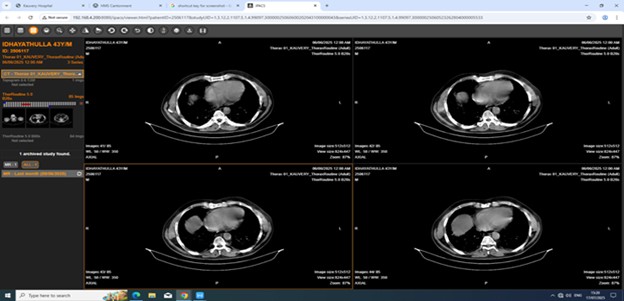

Imaging examination

CT Thorax

Reticular opacity with interstitial septal thickening with traction bronchiectasis in bilateral lung fields with subpleural and lower lobe predominance, Reactive mediastinal lymphadenopathy